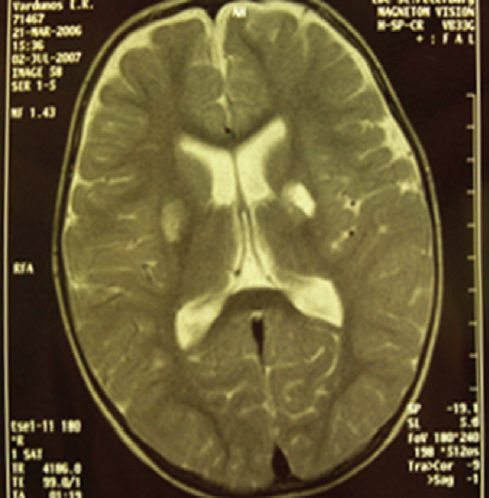

In this study, 23 % of pediatric patients with PM of hemophilic and meningococcal etiologies had foci of pathological MR signal caused by vasculitis with multiple small ischemic zones of various sizes, round or oval in shape, with indistinct contours, which were localized in both the subcortical and periventricular regions of the white matter (Fig. 1). DWI MRI in 63 % of children showed multiple bilateral foci of infarcts, most likely due to small-vessel vasculitis (Fig. 2).

Fig. 1. MRI of a child, 1,9 years old. Diagnosis: Purulent meningitis of hemophilic etiology. Acute ischemic cerebral circulation disorder in the basin of the right middle cerebral artery. T2-VI mode. In the basal structures on the right, a zone of high signal intensity with dimensions of 1.8 × 1.2 × 1.4 cm with fuzzy contours is determined. In the basal regions on the left – a lacunar cyst measuring 1.4 × 0.9 × 1.1 cm / Рис. 1. Магнитно-резонансная томограмма головного мозга ребенка, 1 год 9 мес. Диагноз: «Гнойный менингит гемофильной этиологии. Острое нарушение мозгового кровообращения по ишемическому типу в бассейне правой среднемозговой артерии». Режим Т2-ВИ. В базальных структурах справа определяется зона высокой интенсивности сигнала размерами 1,8 × 1,2 × 1,4 см с нечеткими контурами. В базальных отделах слева — лакунарная киста размерами 1,4 × 0,9 × 1,1 см